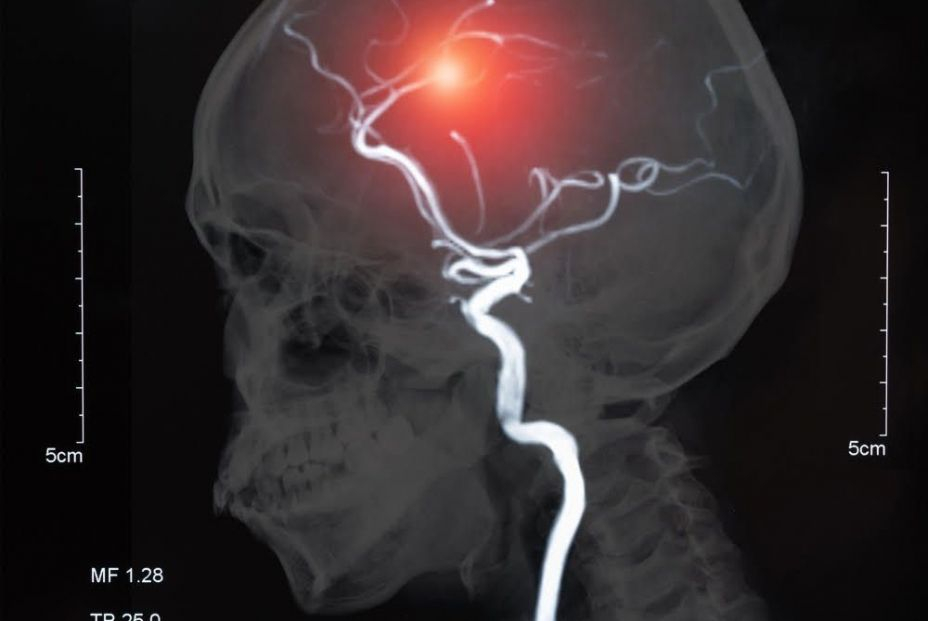

Este estudio exploró estas asociaciones a gran escala en 27 países. El ictus puede producirse por un coágulo (isquémico) o por una hemorragia (hemorragia intracerebral).